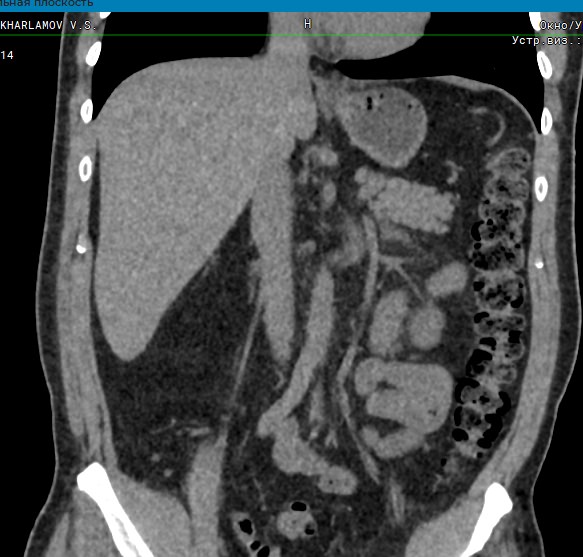

Компьютерная томография позволяет детально визуализировать структуру лимфатических узлов, выявить ее неоднородность, гиперплазию, определить деформацию контуров, появление инфильтрации окружающих тканей с образованием пакетов и конгломератов лимфоузлов.

В ходе сканирования врач оценивает структуру, размеры, плотность, контуры лимфатических узлов этих анатомических областей. Изменения этих параметров могут указывать на: